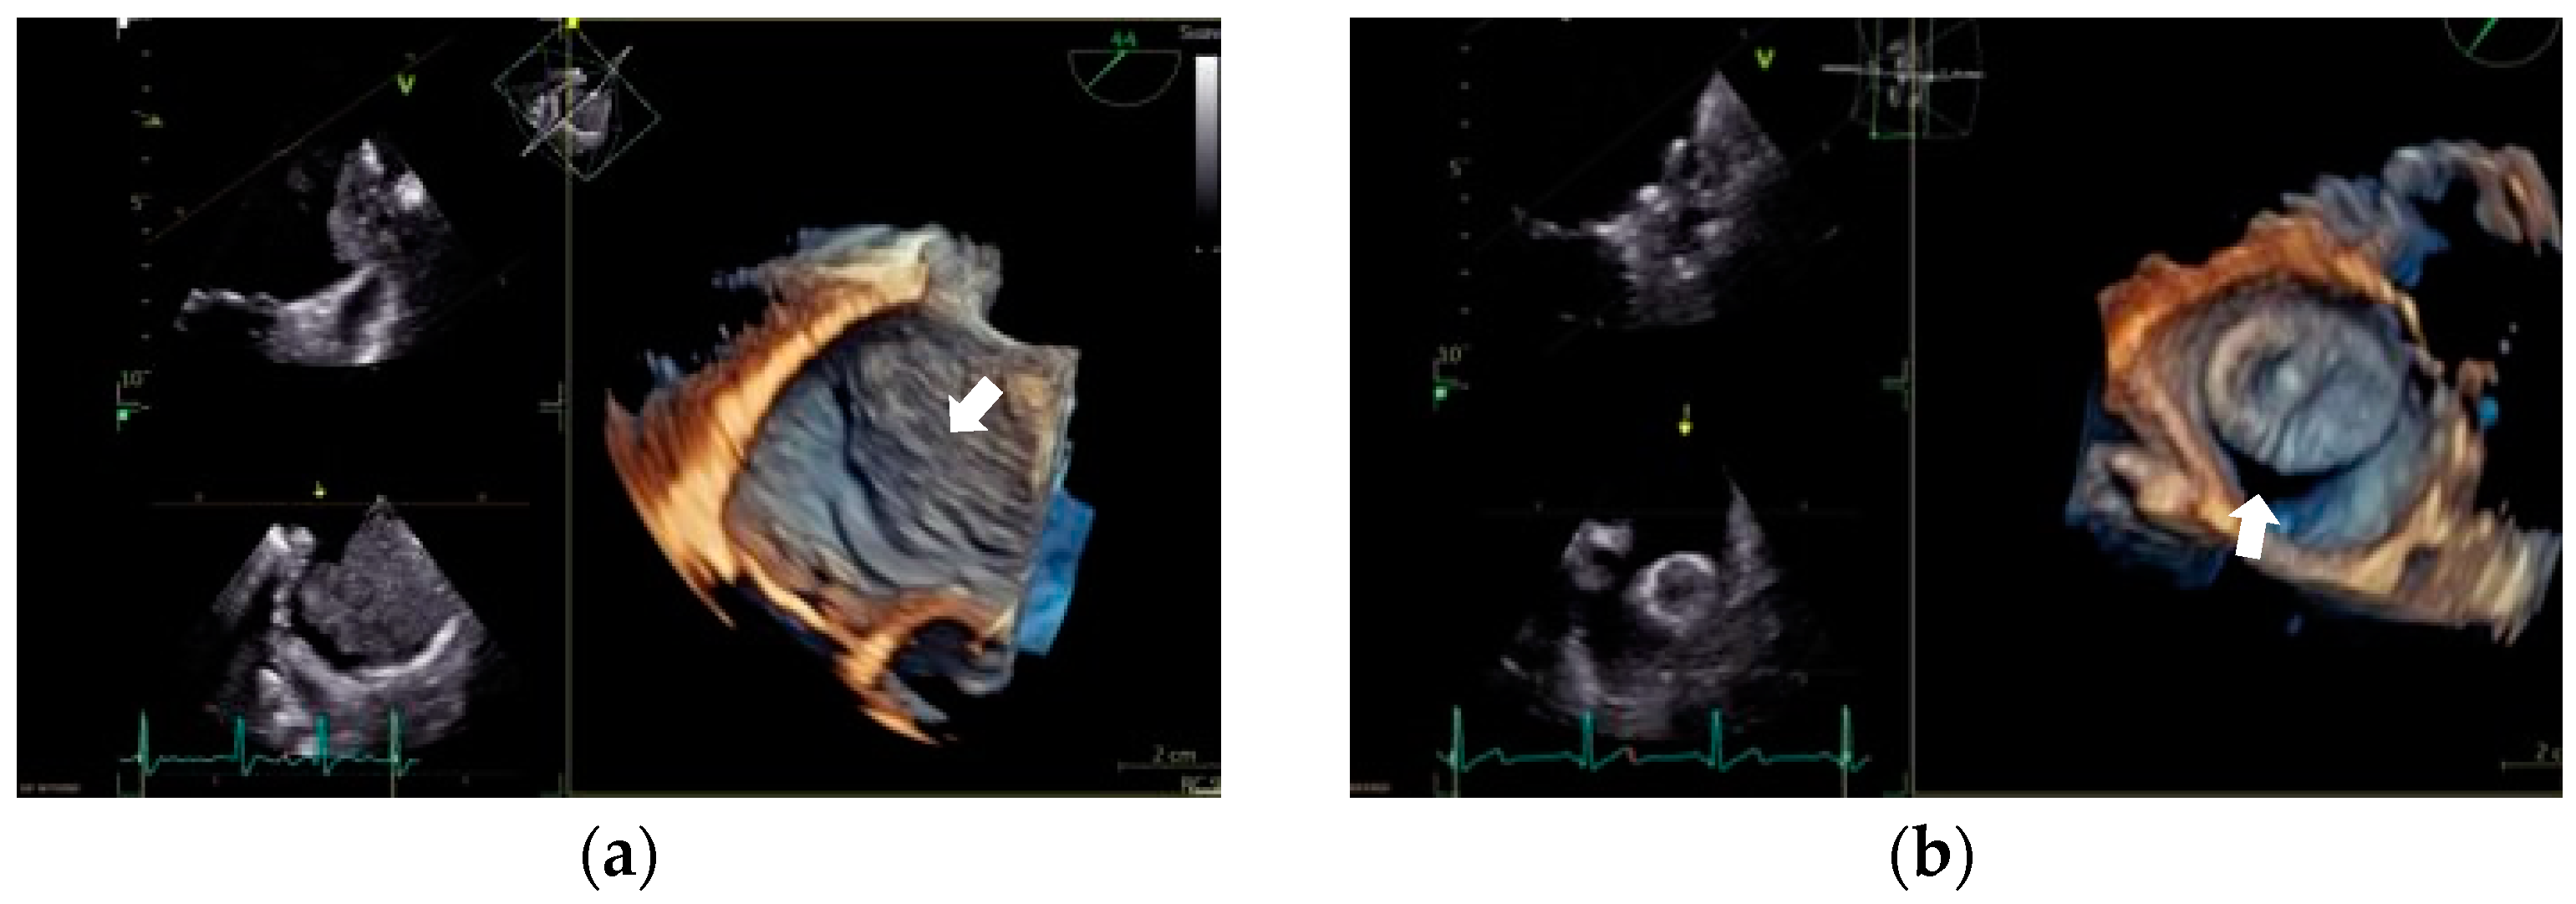

- Kanderian, A.S.; Gillinov, A.M.; Pettersson, G.B.; Blackstone, E.; Klein, A.L. Success of Surgical Left Atrial Appendage Closure: Assessment by Transesophageal Echocardiography. J. Am. Coll. Cardiol. 2008, 52, 924–929. [Google Scholar] [CrossRef] [PubMed]